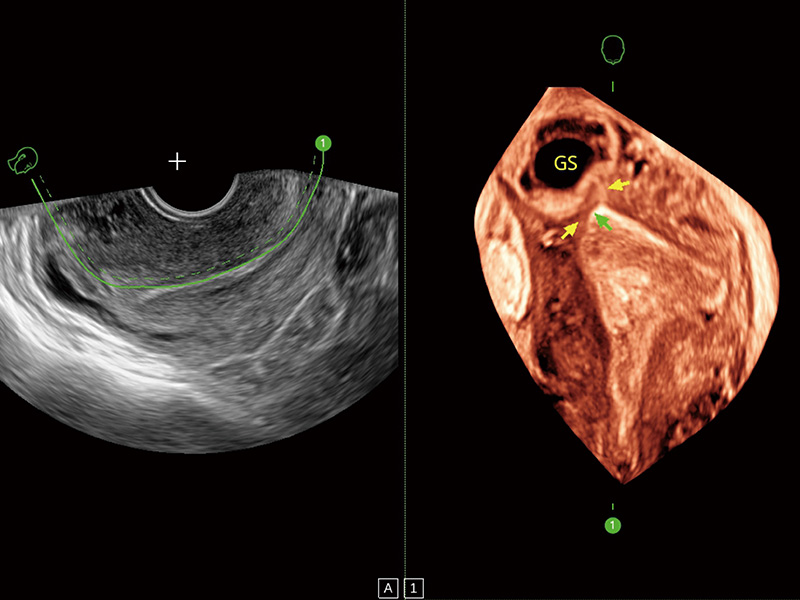

输卵管间质部妊娠